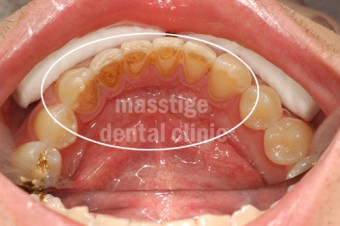

스케일링 치석제거 증례

치료 전 치아상태 : 치석으로 인한 잇몸염증

치료 진행 : 스케일링 치석제거 진행